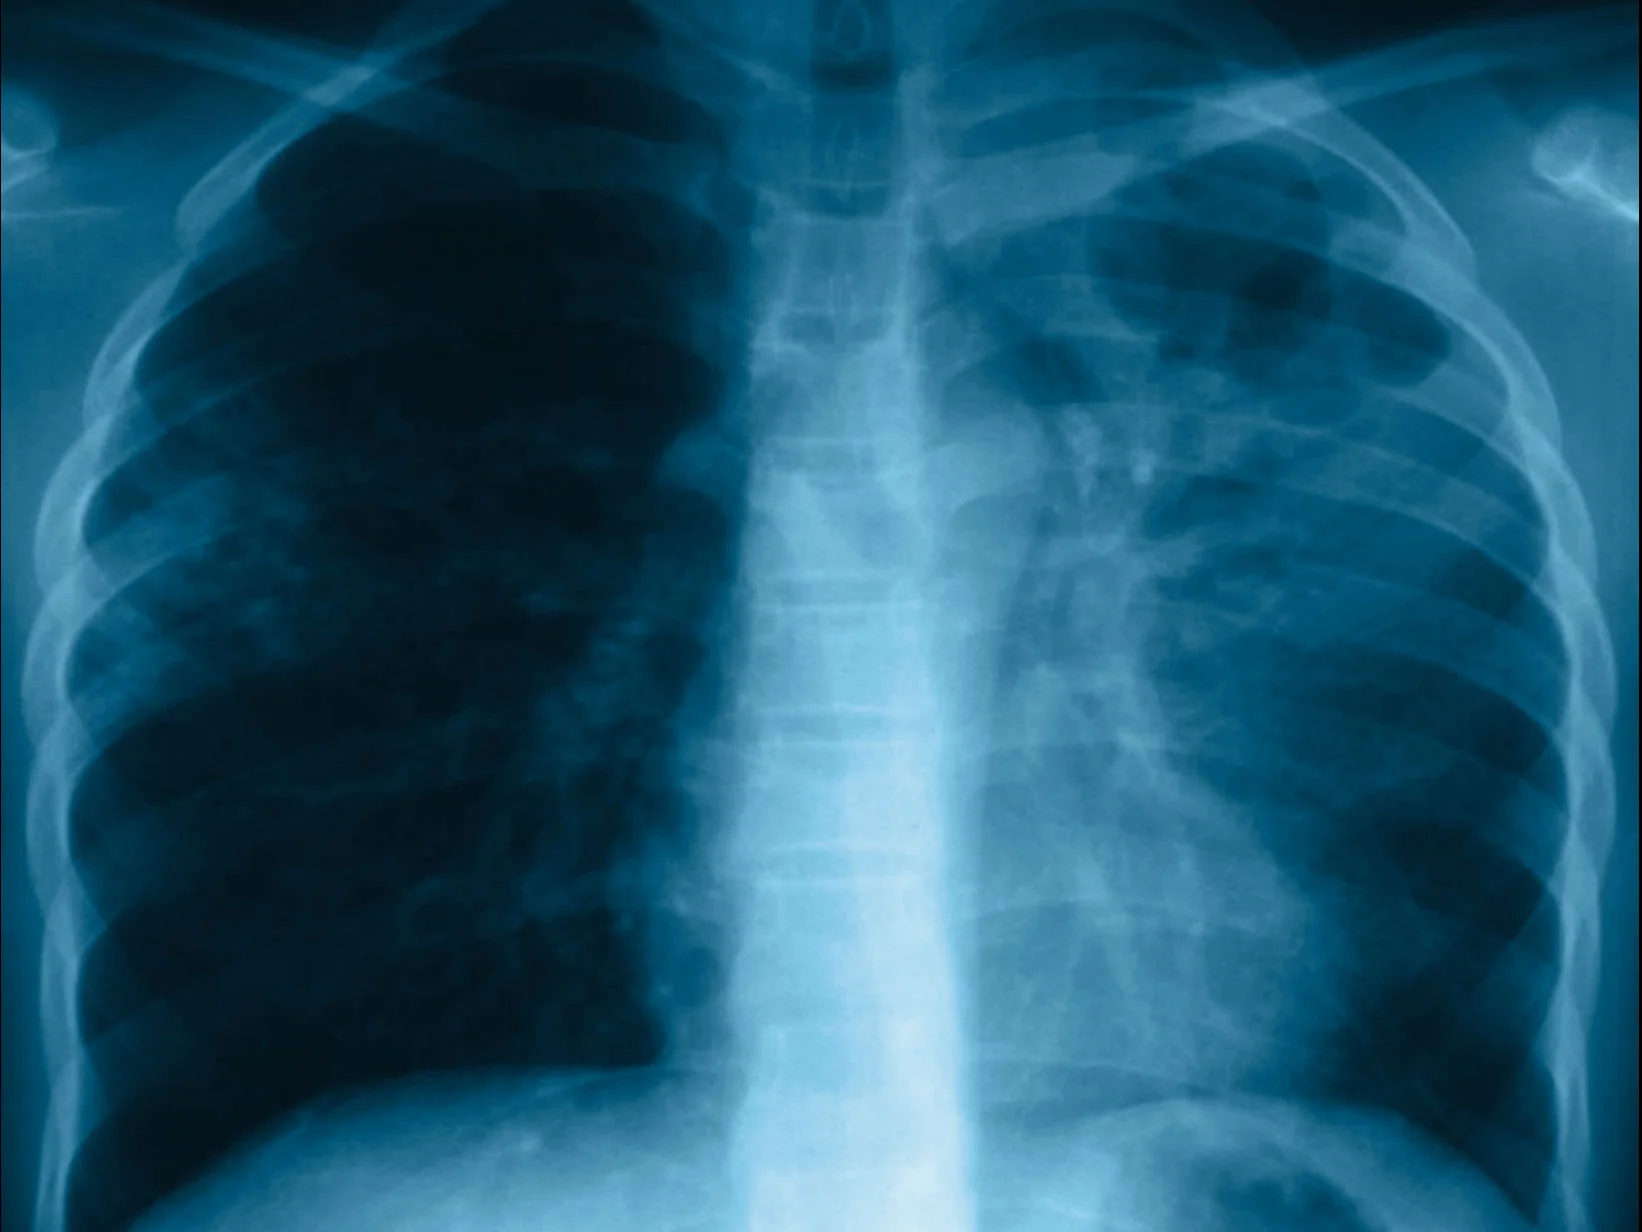

‘ইয়েস! উই ক্যান এন্ড টিবি’। এমনই থিম রাখা হয়েছে ২০২৪-এর ওয়ার্ল্ড টিবি ডে উপলক্ষে। টিবি অর্থাৎ, টিউবারকুলোসিস বা, যক্ষ্মা এখনও পৃথিবীর অন্যতম একটি প্রাণঘাতী অসুখ। এবং, কয়েক বছর ধরে টিবি-কে কেন্দ্র করে আতঙ্ক, উদ্বেগ আরও বেড়ে চলেছে বিশেষ করে মাল্টি ড্রাগ রেজিস্ট্যান্ট টিবি-র কারণে। এ দিকে, কেন্দ্রীয় সরকারের ঘোষণা অনুযায়ী ২০২৫-এর মধ্যে ভারতে টিবি নির্মূল করার লক্ষ্য রয়েছে। এই ধরনের পরিস্থিতির মধ্যে ২৪ মার্চ বিশ্বের বিভিন্ন প্রান্তে পালিত হচ্ছে ওয়ার্ল্ড টিবি ডে। টিবি নিশ্চিহ্ন করার লক্ষ্যে অঙ্গীকার, অনুপ্রেরণা এবং কাজের পুনর্মূল্যায়নের জন্য এই দিনটি একটি সুযোগ বলে জানিয়েছে বিশ্ব স্বাস্থ্য সংস্থা (হু)। ওয়ার্ল্ড টিবি ডে বা বিশ্ব যক্ষ্মা দিবস উপলক্ষে জনস্বাস্থ্য বিশেষজ্ঞ, চিকিৎসক সজল বিশ্বাসের সাক্ষাৎকারটি নিয়েছেন পুবের কলম-এর প্রতিবেদক বিশ্বজিৎ ঘোষ।

উত্তর: টিবি-র জন্য যখন কোনও ওষুধের আবিষ্কার হয়নি, সেই সময় টিবি মানে কার্যত ছিল মৃত্যুর পরোয়ানা। ‘যার হয় যক্ষ্মা, তার নাই রক্ষা।’ এই প্রবাদবাক্যটি তখন আতঙ্ক সৃষ্টি করত। কিন্তু এখনও আমরা টিবি নিয়ে আতঙ্ক মুক্ত হতে পেরেছি কি না, এটা বড় একটি প্রশ্ন। কারণ, ভারতে ২০২০-তে টিবি রোগীর সংখ্যা কিছুটা কমলেও, যথাযথ নজরদারির অভাবে ২০২১-এ এই সংখ্যা বেড়েছে ১৯ শতাংশ। বর্তমানে প্রতি বছর ২৬ লক্ষেরও বেশি মানুষের টিবি নির্ণয় হয়। এ দিকে, এই রোগ নির্ণয়ের বাইরে থেকে যান, এমন মানুষের সংখ্যা আরও বেশি। এ দেশে বছরে চার লক্ষেরও বেশি রেজিস্ট্যান্ট টিবি রোগীর খোঁজ পাওয়া যাচ্ছে। এখনও এ দেশে প্রতি তিন মিনিটে একজন করে টিবি রোগীর মৃত্যু হয়। টিবির ওষুধের অনিয়মিত সরবরাহের বিষয়টিও রয়েছে। এমন সব উদ্বেগজনক পরিস্থিতির মধ্যে আতঙ্ক আরও বেড়ে চলছে।